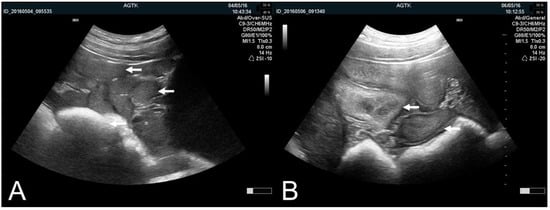

3.1.1. The Pregnant Uterus, Pregnancy Determination and Peripartum Assessment